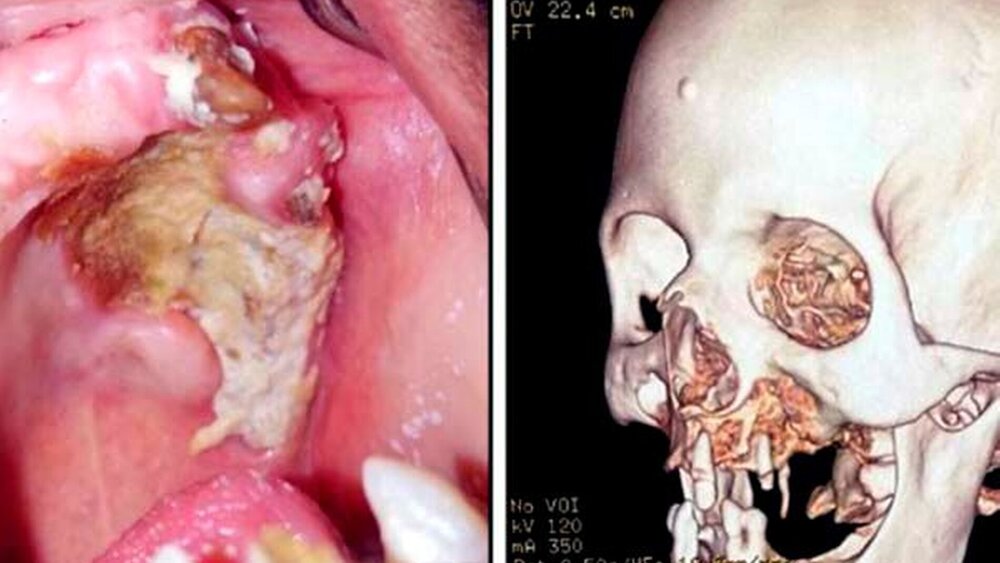

Die Pilzsporen werden eingeatmet und befallen meist zunächst die Nasennebenhöhlen, breiten sich dann aber schnell über die Gefäße auf den Oberkiefer und Gaumen aus. „Die Mucor-Hyphen haben eine Affinität zu Blutgefäßen, dringen in diese ein, vermehren sich und breiten sich in den Gefäßwänden aus, was zu einer Reihe von Ereignissen wie Thrombose, Ischämie, Nekrose und schließlich zur Sequestration des betroffenen Gewebes führt“, schreiben die Autoren die Forschenden [Said Ahmed et al., 2021]. Unbehandelt befällt die Infektion den Gesamten Gesichtsschädel. Bei rund der Hälfte der Erkrankten endet eine Mukormykose letal.

Forschende haben versucht, die Zusammenhänge mit COVID-19 genauer zu ergründen. Hierfür untersuchten sie in Ägypten 14 Patienten (10 Männer und 4 Frauen), bei denen zwei bis vier Wochen nach einer COVID-19 Infektion Symptome einer Mukormykose auftraten. Klinisch äußerte sich diese durch Schmerzen im Gesichtsbereich sowie freiliegendem, nekrotischem Knochen der Maxilla, aber auch übergreifend auf umliegende Bereiche wie die Orbita.

Einige Erkrankte erlitten Zahnverlust im Oberkiefer. Bei allen wurden Röntgenaufnahmen angefertigt sowie eine Inzisionsbiopsie und eine histologische Untersuchung vorgenommen. Therapeutisch wurde Fluconazol eingesetzt, außerdem wurden Tauchgänge in hyperbarem Sauerstoff durchgeführt. Die nekrotischen Knochenareale wurden je nach Befall einer Kürettage und einem Debridement unterzogen; teilweise musste großflächig Knochen entfernt werden.